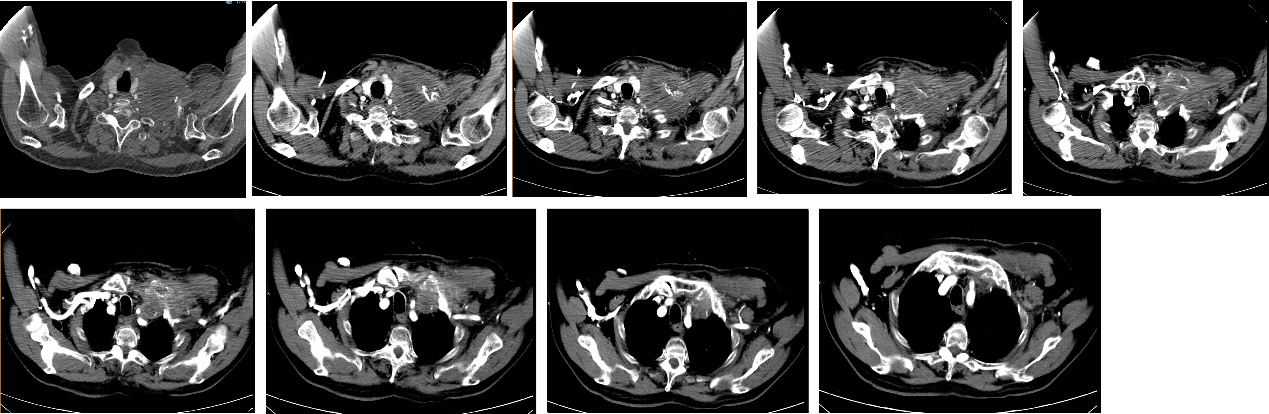

2025-02,患者因“咳嗽伴胸闷1周”于外院就诊,查胸部CT:左肺上叶软组织肿块(大小约4.3cm);左肺上叶癌性淋巴管炎可能;纵隔及左肺门淋巴结增大,恶性可能。

2025-02-25起,予肺癌病灶及相关淋巴引流区放疗P_GTV Dt 66Gy/30Fx。

2025-03-11,患者放疗期间复查CT:左肺上叶MT复查:病灶范围较前缩小;两肺微小结节;两肺少许条索;左肺门及纵隔内结节样淋巴结;左侧胸腔少许积液(较前减少);左侧胸膜稍增厚;动脉硬化;附见:胆壁稍增厚。

2025-03-26,复查CT:左肺上叶MT复查:病灶范围较前片缩小;两肺微小结节;两肺少许条索;左肺门及纵隔内结节样淋巴结;左侧胸膜稍增厚;动脉硬化;附见:胆囊壁稍增厚。

疗效评估:PR。

2025-08-13,复查CT:1. 左肺上叶MT复查:病灶较2025-06-03局部稍缩小,斑片条索影较前增多;两肺微小结节,部分伴钙化(较前相仿);两肺少许条索;右肺肺大疱;左肺门及纵隔内结节样淋巴结(较前相仿);双侧胸膜稍增厚;动脉硬化;左侧膈膨升。2. 胃底部结节样增厚,建议结合胃镜及组织学检查;肝左叶一过性高灌注;胆壁稍增厚;右肾小囊肿;胃窦壁稍增厚;腹膜后结节样小淋巴结;附见:L2椎体轻度楔形变及双侧椎弓峡部裂,请结合MR;L2、3椎体不稳;L4-5椎间隙变窄。